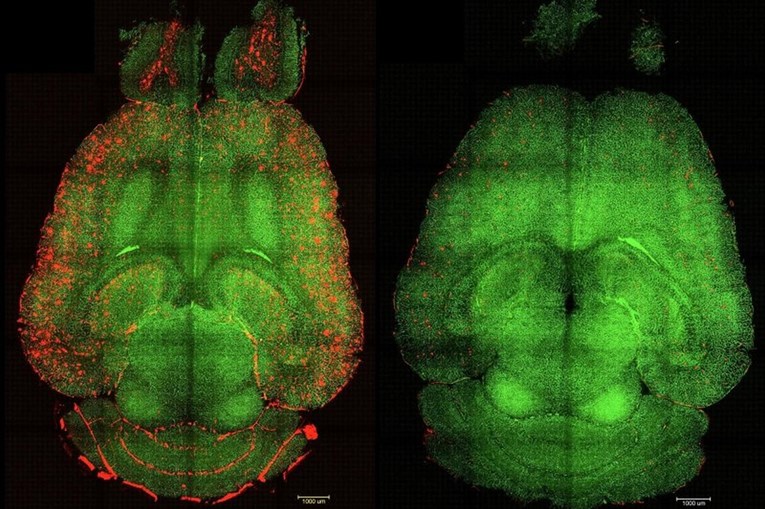

Во серија експерименти на генетски модифицирани глувци, кои произведуваат големи количини на амилоид-бета протеин и покажуваат пад на когнитивната функција, администрацијата на супрамолекуларни лекови доведе до речиси моментално намалување на нивоата на протеинот. „Само еден час по инјекцијата, видовме намалување од 50-60 проценти на количината на амилоид-бета протеин во мозокот“, рече коавтор и истражувач од болницата Западна Кина на Универзитетот Сечуан.

Она што е особено возбудливо е откритието дека когнитивните подобрувања кај глувците биле значајни. Глувчето, кое би било еквивалентно на 90-годишен човек, „го вратило однесувањето на здрав глушец“ шест месеци по примањето на третманот. „Долгорочниот ефект доаѓа од враќањето на васкулатурата на мозокот“, објасни Батаља.